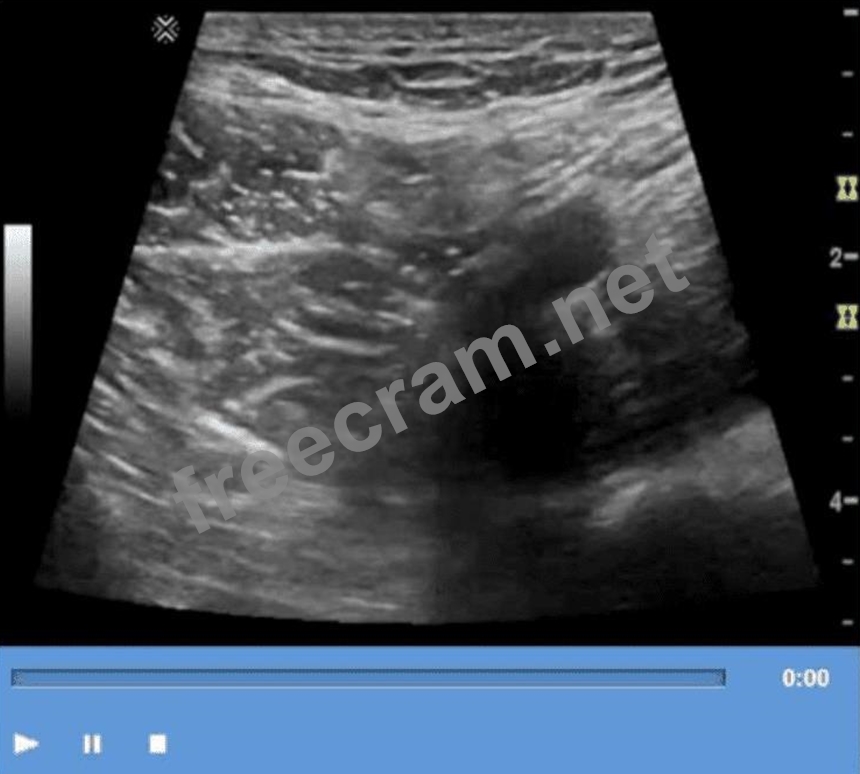

Which technique is used to demonstrate the finding in this video?

Question 19: Which technique is used to demonstrate the finding in this v...